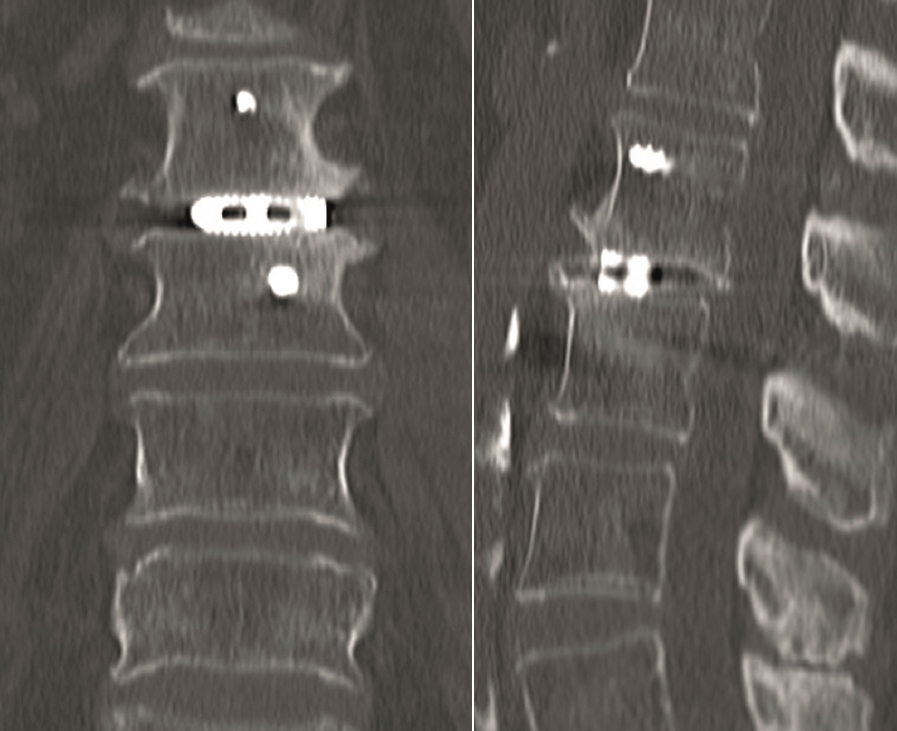

Case 4 : ALIF L4-L5 non union

A 40-year-old man 5 years after ALIF L4-L5 using SynFix with axial low back pain. The CT scan shows locked pseudarthrosis (Fig 17). Nonoperative treatment failed. The treatment option was bilateral Facet Wedge at L4-L5.

A less invasive approach was used with Insight Retractor using the bilateral Facet Wedge. No bone graft. X-ray follow-up after 3 months and CT assessment after 6 months (Fig 18-19).